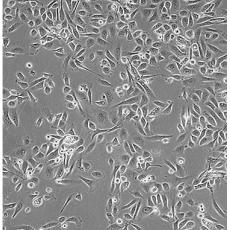

產(chǎn)品名稱 PC-3(PC 3)

中文名稱 人前列腺癌細胞

組織來源 前列腺癌;骨髓轉(zhuǎn)移;男性

細胞種屬 Homo sapiens, human

生長特性 adherent

培養(yǎng)基 Ham's F-12K+10% FBS+1% P/S

形態(tài)特征 epithelial

傳代方法 1:3-1:6

細胞描述 PC-3源于一位62歲白人男性IV級前列腺腺癌患者的骨轉(zhuǎn)移灶;有低水平的酸性磷酸酶活性和5-α-睪酮還原酶活性。